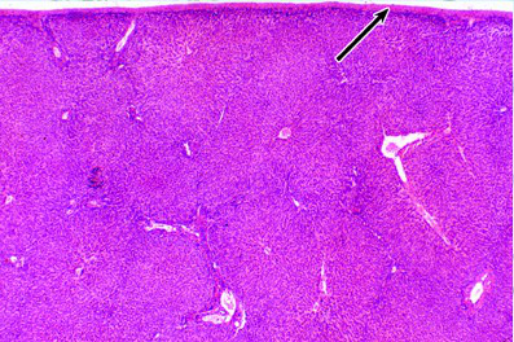

肝(左猪肝、右人肝)

肝小叶

中央静脉: